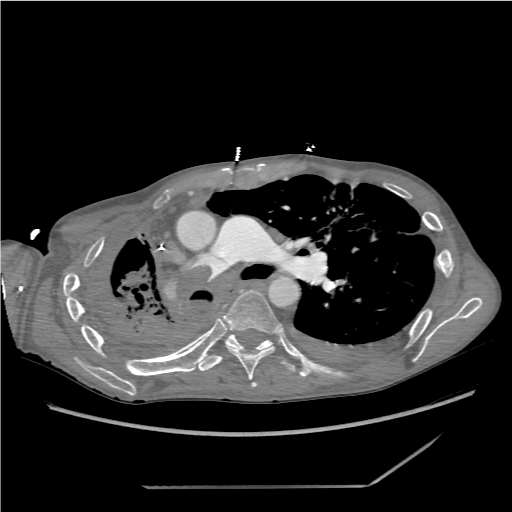

Due to its association with H. capsulatum, most patients usually have a diagnosis via serological assay or bronchioalveolar lavage [11,18]. Definitive diagnosis for histoplasmosis has been achieved via antibody titers or Grocott methenamine silver stains revealing H. capsulatum [11]. There is no definitive laboratory assay to diagnose FM. Due to its host immune modulated response, some genetic markers related to human leukocyte antigen markers has been identified, however more definitive studies are lacking [19]. Chest radiographs (Figure 2) can assist in diagnosis, usually showing enlarged perihilar and mediastinal lymph nodes. It is important to note that some chest radiographic findings are non-specific, including widening of the mediastinum, cavitary lesions, and adenopathy, prompting further workup with chest Computerized Tomography (CT) and/or bronchoscopy [8] (Figure 3 and Figure 4). Chest CT usually shows focal or diffuse fibrosis, usually confined to the middle mediastinum [20]. The focal appearance of the fibrosis appears more frequently in cases of FM than the diffuse pattern. Rarely is the posterior mediastinum involved [21]. As with most cases of FM, contrast enhanced imaging will depend on the structures involved. If vasculature is involved, contrast enhanced CT will benefit in confirming the diagnosis (Figure 5 and Figure 6). Other modalities, including MRI, esophagram or contrast pulmonary arteriogram may be useful to rule out malignancy or other mass effect causing lesions. It is important to note that the other modalities are not as efficient in representing the degree of calcification and fibrosis, therefore CT imaging should be the modality of choice if FM is suspected [8,20,22].

Figure 5: CTA Chest Contrast showing encroachment of main pulmonary artery by disease. View Figure 5